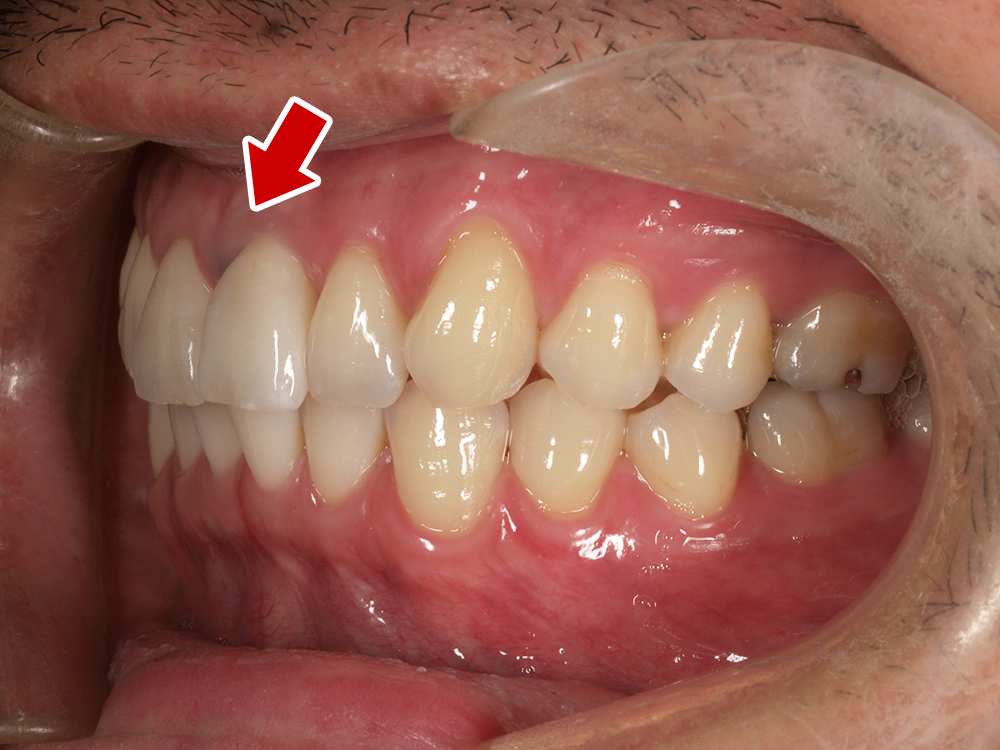

オールオン4は、片顎につき最少4本のインプラントで連結ブリッジを固定し、失われた歯列をまとめて再建する方法です。

骨がしっかり残っている部位を選び、奥歯には角度をつけて埋入することで安定性を確保します。手術当日に仮歯を装着できるため、歯のない期間を過ごす必要がありません。

オールオン4の大きなメリットの一つは、見た目の美しさです。

オールオン4の上部構造(被せ物)は、前歯から奥歯までがつながったブリッジ状になっており、失われた歯茎の部分も人工の素材で再現されます。

そのため、歯の大きさや歯並び、歯茎の引き締まり具合まで理想的にデザインされた、自然で美しい仕上がりが期待できます。

さらに、歯茎部分を人工の素材で補うことで、唇を内側から支える「リップサポート」も回復でき、若々しい印象を取り戻すことができます。